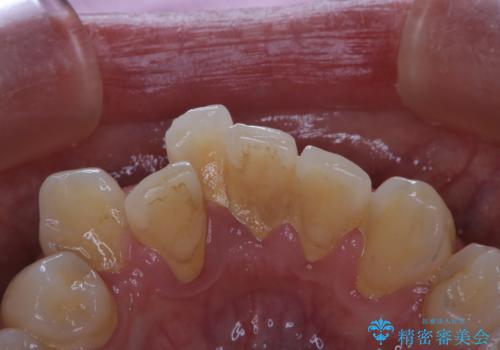

プラークが放置されると、そこで歯周病菌が繁殖し始めます。よって歯肉に炎症が生じ、歯周病に引き金となります。

PMTC(保険外治療)は、毎日の歯磨きで落としきれない汚れや、コーヒ、紅茶・タバコのヤニなどの着色も除去します。目には見えない歯と歯の間・歯肉の境目などに残っているプラーク(歯垢)もしっかり取り除きます。PMTCでは専門的な機械や材料を使用して、徹底的に汚れを除去するため、虫歯・歯周病・口臭予防などにつながります。

またPMTCを行うことで、ご自身本来の歯の色になり自然な明るさになります。